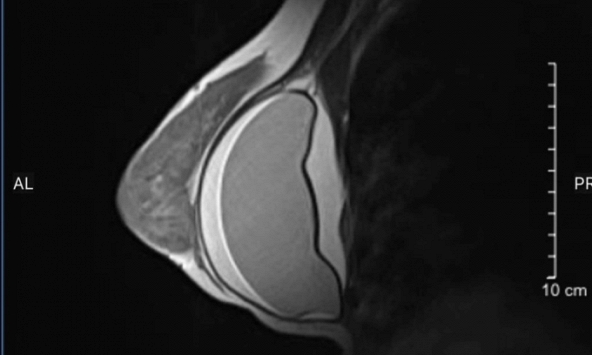

Kết quả kiểm tra cho thấy túi ngực bên phải đã bị rách, một phát hiện khiến chính chị cũng bất ngờ. Các bác sĩ sau đó tư vấn nên phẫu thuật nội soi lấy túi ngực ra sớm, bởi nếu để kéo dài, tình trạng rách túi có thể dẫn tới viêm, xơ hóa hoặc làm tăng nguy cơ biến chứng nguy hiểm cho sức khỏe.

Ảnh minh họa

Điều đáng lưu ý là trong suốt thời gian trước đó, cơ thể không phát đi bất kỳ "tín hiệu cảnh báo" rõ ràng nào. Trường hợp này cho thấy tổn thương túi độn ngực có thể diễn tiến âm thầm, không kèm theo triệu chứng lâm sàng dễ nhận biết và chỉ được phát hiện khi kiểm tra bằng các phương pháp chẩn đoán hình ảnh chuyên sâu.